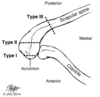

AC separation classification

I: sprain

II: 25-100% displacement

III: >100% displacement

IV: Posterior

V: >300% through trapezius

VI: Subcoracoid